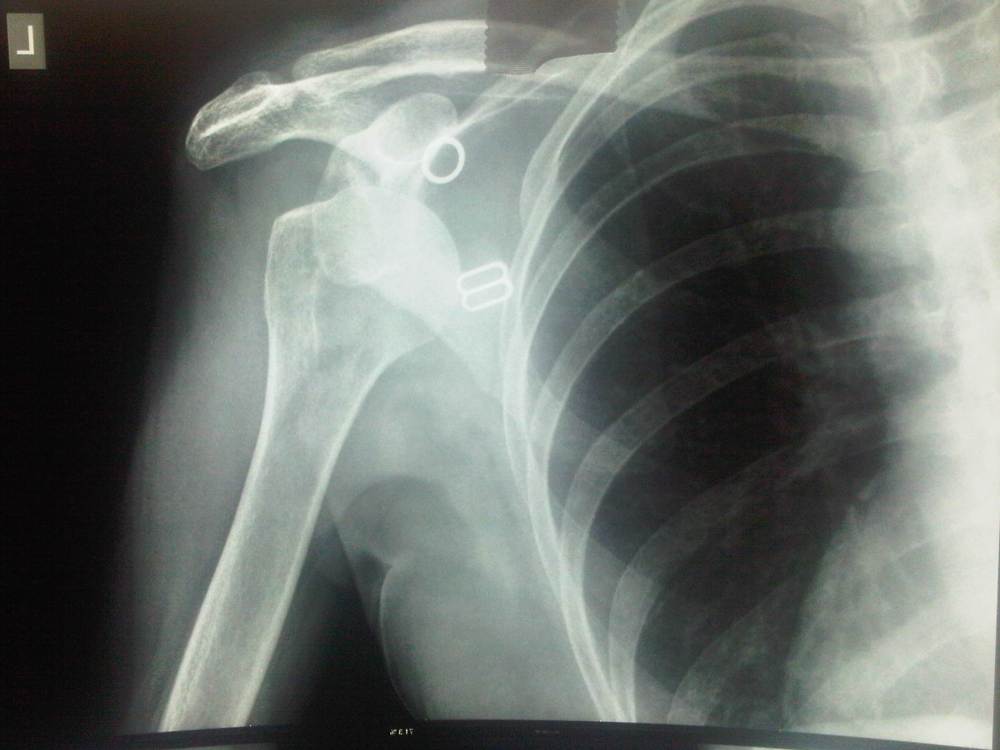

Ikke nok med det. Nemesis tillader sig også den frækhed at sparke Annette omkuld på byggepladsen på taget så hun falder og vrider sin skulder af led – så afsted til Ciwec Clininc og få den vredet på pladst igen.

Det gør ondt som ind i HELVEDE.

Nu sidder fruen med armen i en af de mest ophidsende slynger man kan forestille sig: